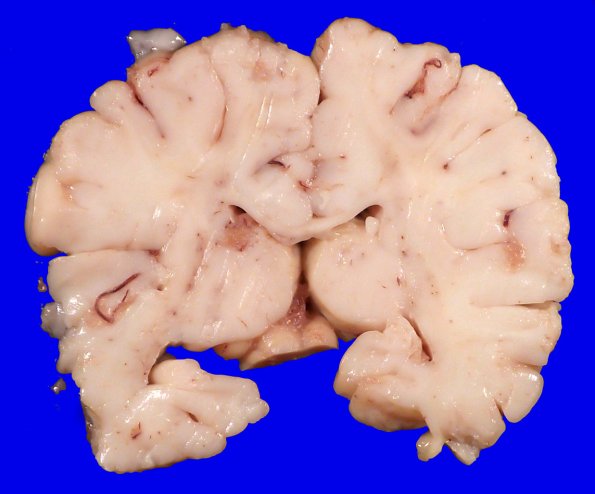

4A3 Menkes Dz (Case 4) Gross 3

Coronal sections of the brain appear appropriate for the patients age.